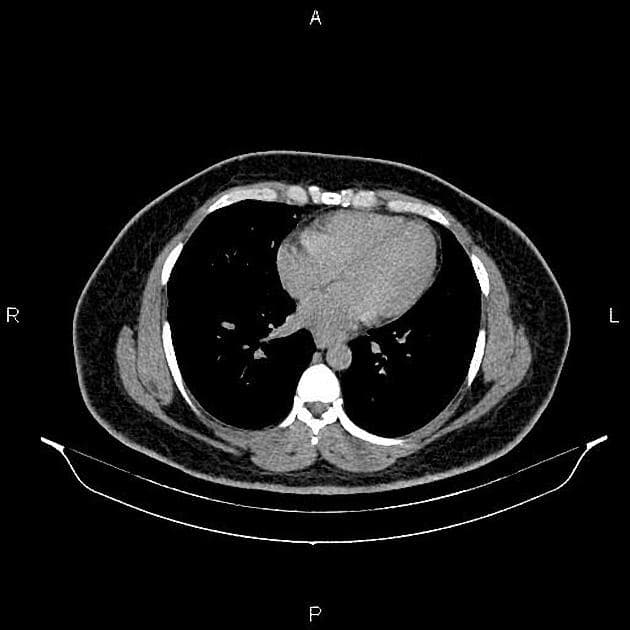

- Tụy to.

- Cả tụy và mô mỡ quanh tụy vùng sau phúc mạc đều tăng tín hiệu, gợi ý phù.

- Gan có bờ dạng nốt và mô đệm không đồng nhất, kèm theo lách to, phù hợp với xơ gan và tăng áp lực cửa.

- Có một lượng nhỏ dịch ổ bụng.

Nghiên cứu này cho thấy phù tụy có thể là hậu quả của suy gan mất bù, và tình trạng phù này có thể xuất hiện trước khi có dịch ổ bụng. Đây là một tình huống hiếm gặp, nhưng rất hữu ích trong việc làm rõ các tiêu chuẩn chẩn đoán viêm tụy cấp theo Phân loại Atlanta sửa đổi năm 2013:

Ở bệnh nhân này, chỉ có hình ảnh học gợi ý viêm tụy cấp, trong khi không có triệu chứng lâm sàng và men tụy bình thường, do đó không chẩn đoán viêm tụy cấp.